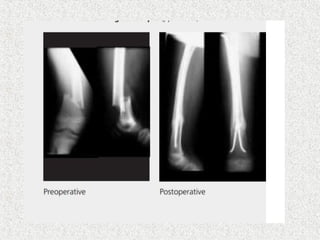

 Closed unstable#  Irreducible #  Polytrauma  Always descending technique  Medial & lateral of tibial tuberosity  Nail tip curved posteriorely-antecurvation